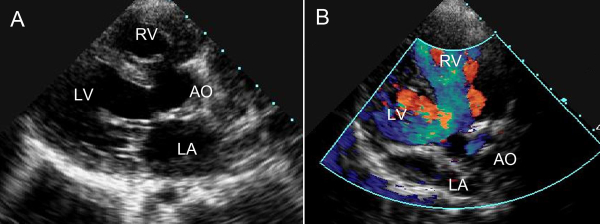

彩色多普勒超声对心脏及血管病变的诊断:

彩色多普勒超声能够同时评价血管的二维结构和实时血流动力学变化。我院超声科已开展此项技术。

1、超声心动图能够显示心脏结构,观察血流状态,评估心脏功能及治疗效果,其临床应用价值已得到大家的公认。